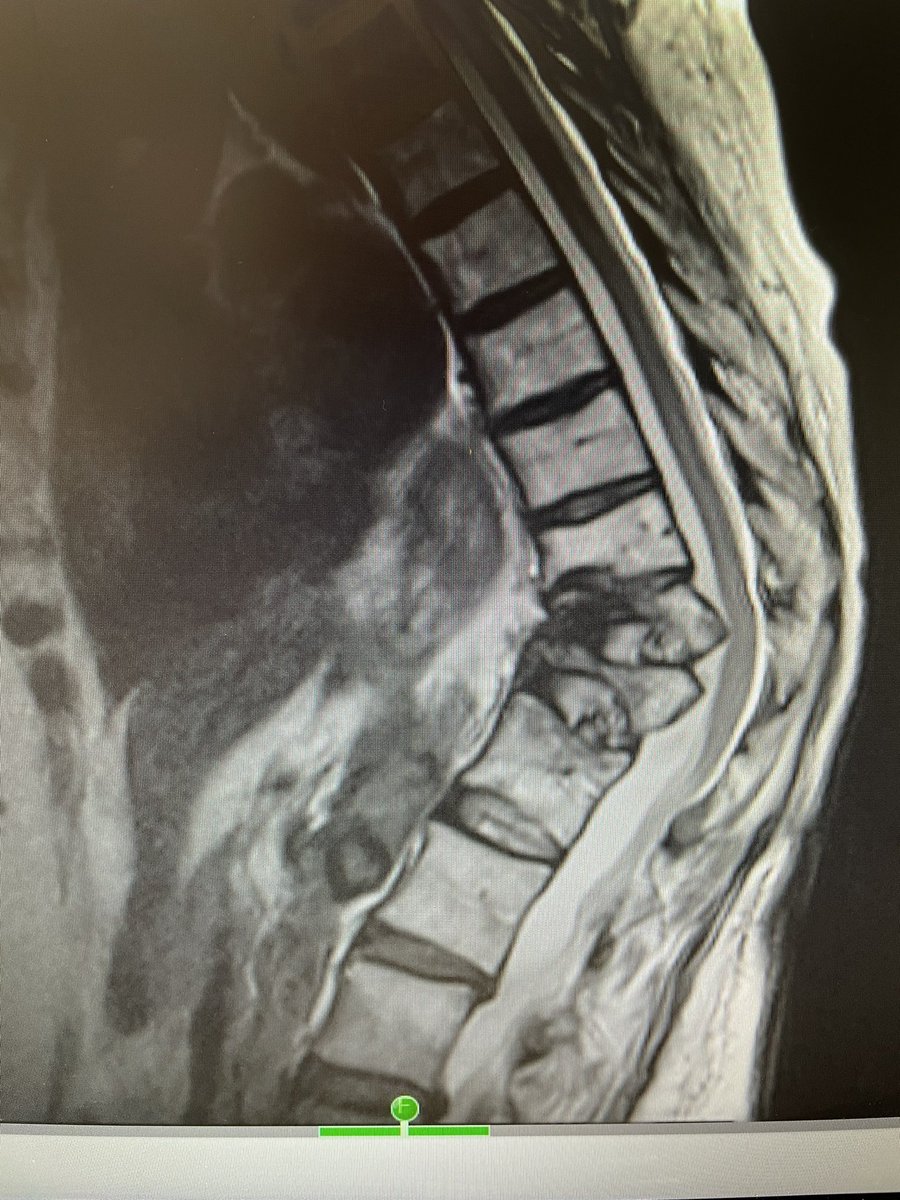

@drcostantino1 probably pass on vertebral augmentation.......